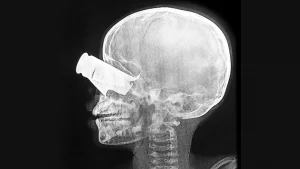

Un niño de nueve años llegó al hospital apoyado por MSF en Tine, Chad, en febrero, tras un ataque con drones en el oeste de Sudán. Presentaba una gran herida de metralla en el ojo, graves fracturas faciales y dos dedos amputados. Fue trasladado a Yamena para recibir tratamiento.

Sudán: Repetidos ataques con drones impactan zonas civiles; MSF atendemos a unas 170 personas en dos semanas